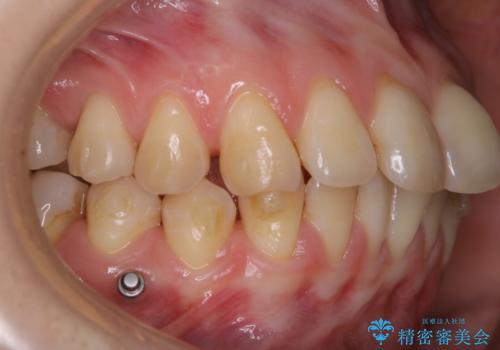

インビザラインでの治療中の患者様のクリーニング前後写真です。

- インビザライン矯正中に茶色が気になるとのことで来院されました。PMTC30分コースを行いました。